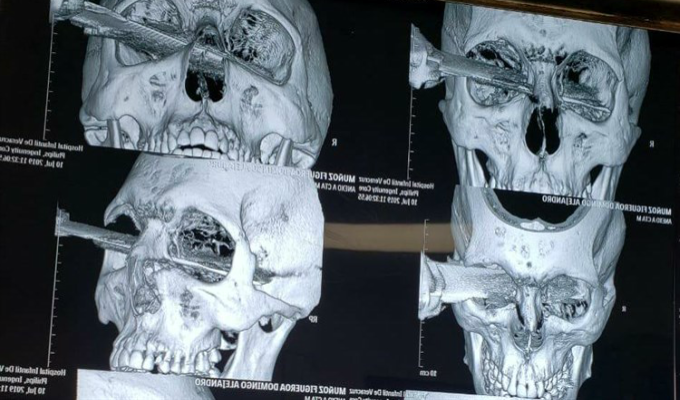

En México, una discusión entre dos hombres, que se disputaban un lugar para aparcar en el estacionamiento de un supermercado, provocó que uno de ellos acuchillara al otro en la cabeza.

Según testigos, la riña fue iniciada por el agredido, quien descendió de su auto para golpear el auto del hombre que, segundos después, le clavó un cuchillo en el rostro, a la altura del ojo izquierdo, según se observa en un video que circula en redes sociales.